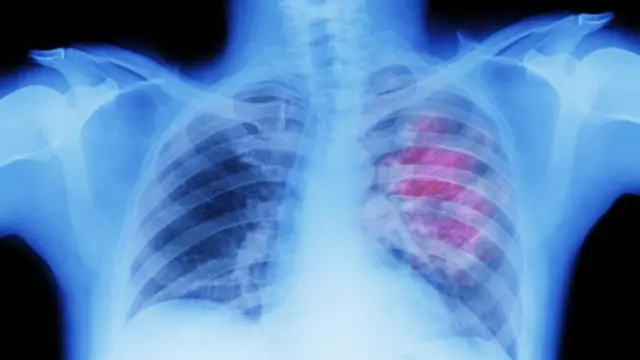

৭. রক্তপাত

ক্যান্সারের ক্ষেত্রে প্রাথমিক অবস্থায় কিংবা তা ছড়িয়ে পড়ার পর অস্বাভাবিক রক্তপাত হতে পারে। কাশির সাথে রক্তপাত ফুসফুসের ক্যান্সারের লক্ষণ হতে পারে।

টানা কাশি ফুসফুসের ক্যান্সারের লক্ষণ হতে পারে। তিন সপ্তাহের বেশি সময় ধরে কাশি থাকলে চিকিৎসকের পরামর্শ নেয়া উচিত।